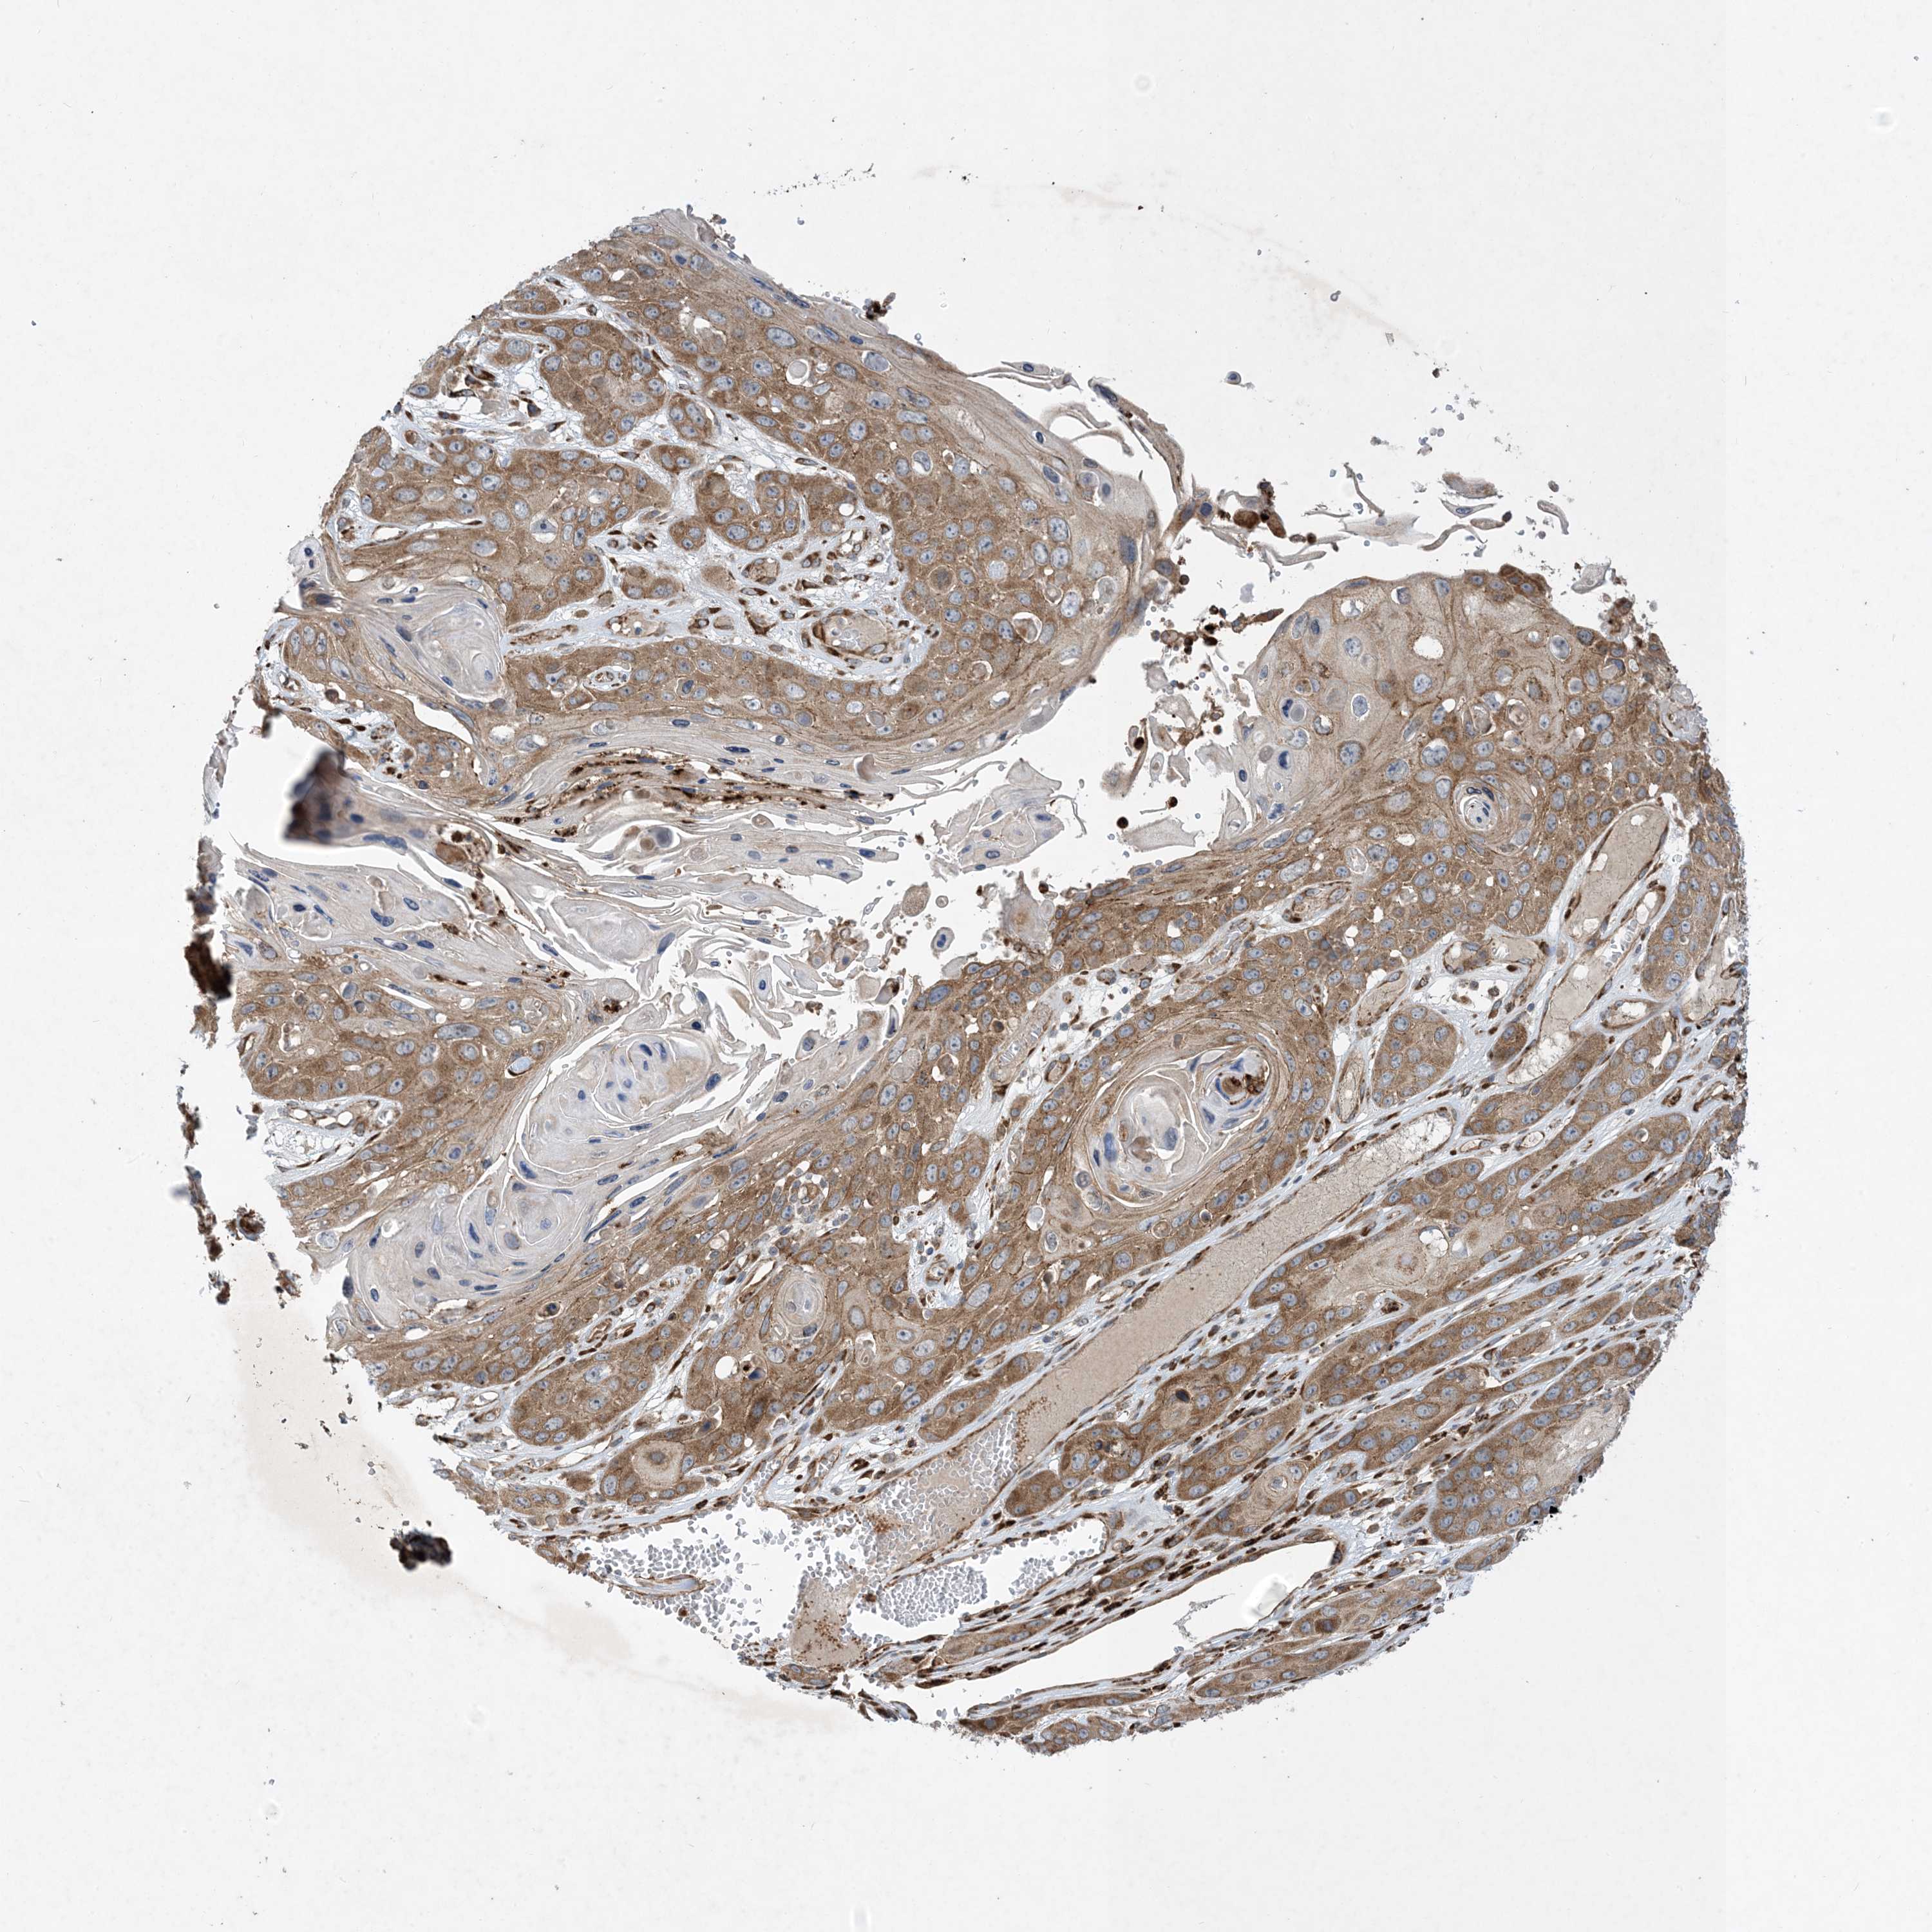

SKIN CANCER - Protein expressioni

A mouse-over function shows sample information and annotation data. Click on an image to view it in a full screen mode. Samples can be filtered based on level of antibody staining by selecting one or several of the following categories: high, medium, low and not detected. The assay and annotation is described here.

Antibody stainingi

Antibody staining in the annotated cell types in the current human tissue is reported as not detected, low, medium, or high, based on conventional immunohistochemistry profiling in selected tissues. This score is based on the combination of the staining intensity and fraction of stained cells.

Each image is clickable and will lead to virtual microscopy that enables deeper exploration of all samples and also displays staining intensity scores, fraction scores and subcellular localization as well as patient and tissue information for each sample.

Antibody HPA035599

Staining

High

Intensity

Strong

Quantity

>75%

Location

Nuclear

Basal cell carcinoma

Squamous cell carcinoma, NOS

Squamous cell carcinoma, metastatic, NOS